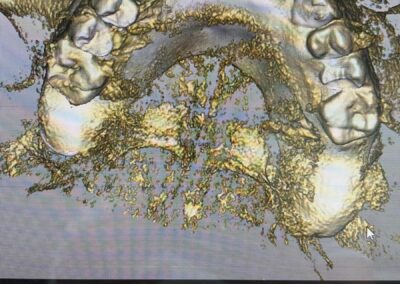

Ein entscheidender Bestandteil dieser modernen Praxis ist die Auswertung von 3D-Daten, die aus der Computertomographie extrahiert werden. Neuere Entwicklungen zeigen auch, dass Daten von optischen Scannern zunehmend in den Planungsprozess integriert werden. Diese umfassenden Informationen, kombiniert mit fortschrittlicher Implantatplanungssoftware, ermöglichen eine akkurate Simulation sowohl chirurgischer als auch prothetischer Phasen.

Vor der eigentlichen Operation können Implantatpositionen sorgfältig festgelegt werden, wobei spezifische Faktoren wie das Knochenvolumen und die -qualitäten, die Lage anatomischer Strukturen (wie Nerven, Gefäße und Nebenhöhlen), prothetische und ästhetische Bewertungen sowie präzise Messungen der Breite und Höhe des Knochens an den vorgesehenen Implantatstellen berücksichtigt werden. Auch die Abstände und Winkel zwischen den Implantaten lassen sich exakt berechnen, was entscheidend für den langfristigen Erfolg der Behandlung ist.

Bilder v.l.n.r.: 01 Herstellung der röntgenopaken Schablone zur Übertragung auf den Dicom-Datensatz / 02 Planung der Zahnimplantatstellung anhand der röntgenopaken Schablone / 03 Virtuelle Planung auf dem 3D-Modell / 04 Übertragung der Röntgenschablone auf dem Dicom-Datensatz (1:1) / 05 Virtuelle Plaung im Dicom-Datensatz / 06 Visualisierung frontal / 07 Visualisierung seitlich / 08 Visualisierung des Implantat-Falles frontal / 09 Visualisierung mit Bohrschablone